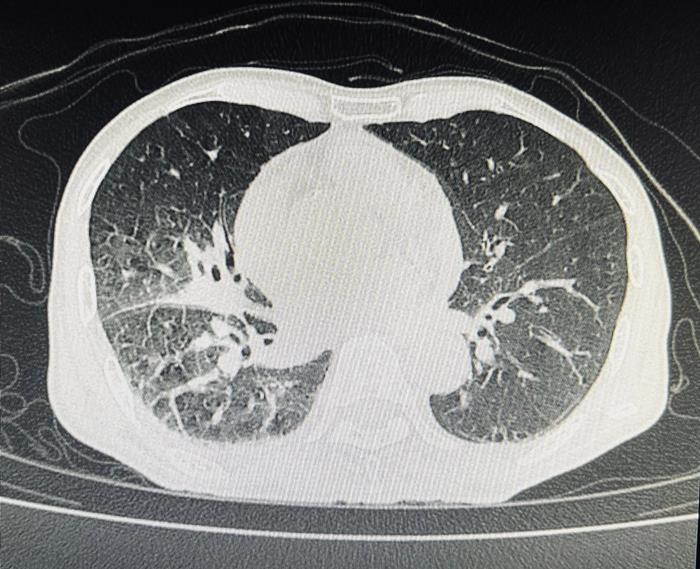

ผู้ป่วยรายนี้เป็นเพศชาย วัย 70 ปี มาด้วยอาการไอเรื้อรัง มีเสมหะปนเลือด หอบเหนื่อยจนเดินไม่ค่อยไหว ผอมจนน้ำหนักลด เมื่อเอกซเรย์ตรวจดู พบว่า มีลักษณะคล้ายปอดอักเสบที่ด้านขวาล่างหรือมีอะไรที่คล้ายก้อนมะเร็งอยู่ตรงนั้น

ฝุ่นถ่านดำเข้ามาในหลอดลม จนเกิดพังผืดและหลอดตีบ

ลามไปสู่เรื่องของปอดติดเชื้อ ปอดอักเสบเนื่องจากการอุดกั้น

เกิดปอดแฟบอย่างที่เห็นในฟิล์มที่คล้ายลักษณะก้อน ๆ

ส่วนสาเหตุที่ไอเรื้อรัง หอบเหนื่อย เพราะหลอดลมและเนื้อปอดผิดปกติ ถ้าเป็นหนักมาก ๆ คือ ฝุ่นถ่านดำจะโดนเนื้อปอดด้วย เรียกว่า โรคปอดถ่านหิน และยังสัมพันธ์กับวัณโรคได้ 20% และเป็นโรคมะเร็งได้ 10%